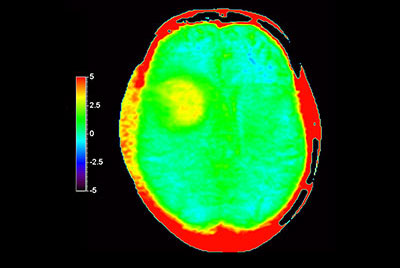

3D APT brain imaging for glioblastoma recurrence

-

Brain astrocytoma post radiotherapy, incl. 3D APT

-

Brain with glioblastoma, incl. 3D APT

-

Brain lesion with 3D APT

-